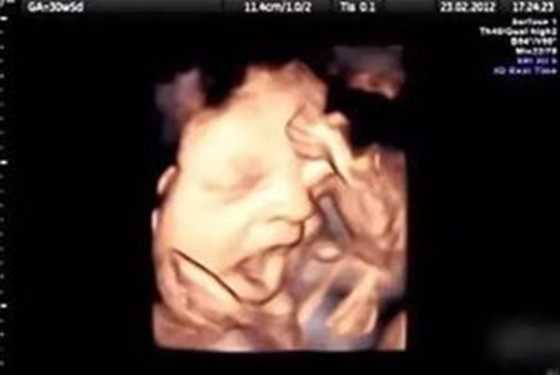

1、吮吮手解解闷

待在羊水里,胎宝宝会闷得慌,总想着自己能找点乐子呢!瞧,无聊的Ta,又在吮手指了,这是Ta最好的解闷方式。不过准妈咪是感觉不到这种细微的动作的,只有做B超检查时,才有可能偶然捕捉到这个动作哦。